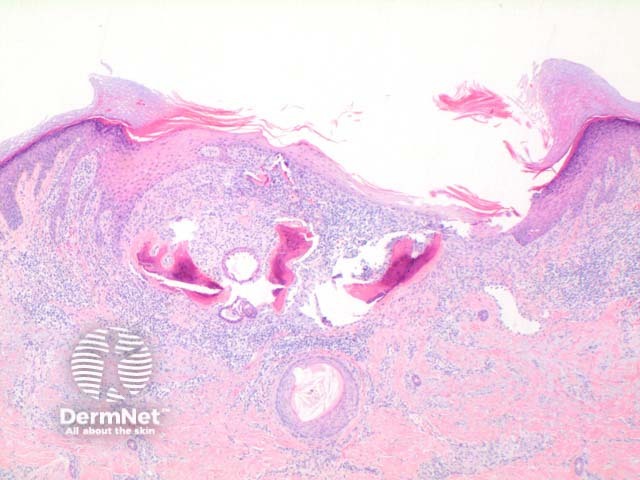

Scanning power of osteoma cutis reveals the presence of dense eosinophilic deposits in the dermis or subcutaneous tissue (Figure 1). Spicules of bone may be seen to perforate the epidermis in the process of transepidermal elimination (Figures 2 and 3). Most cutaneous bone formation occurs by the process of membranous ossification and so associated cartilage tissue is lacking. Bone is identified by osteocytes held within small lacunae (Figures 4 and 5) and the hydroxyapatite eosinophilic support material. In larger deposits, Haversian systems can be seen as concentric osteocytes around a central blood vessel (carried within a Haversian canal).

Figure 1